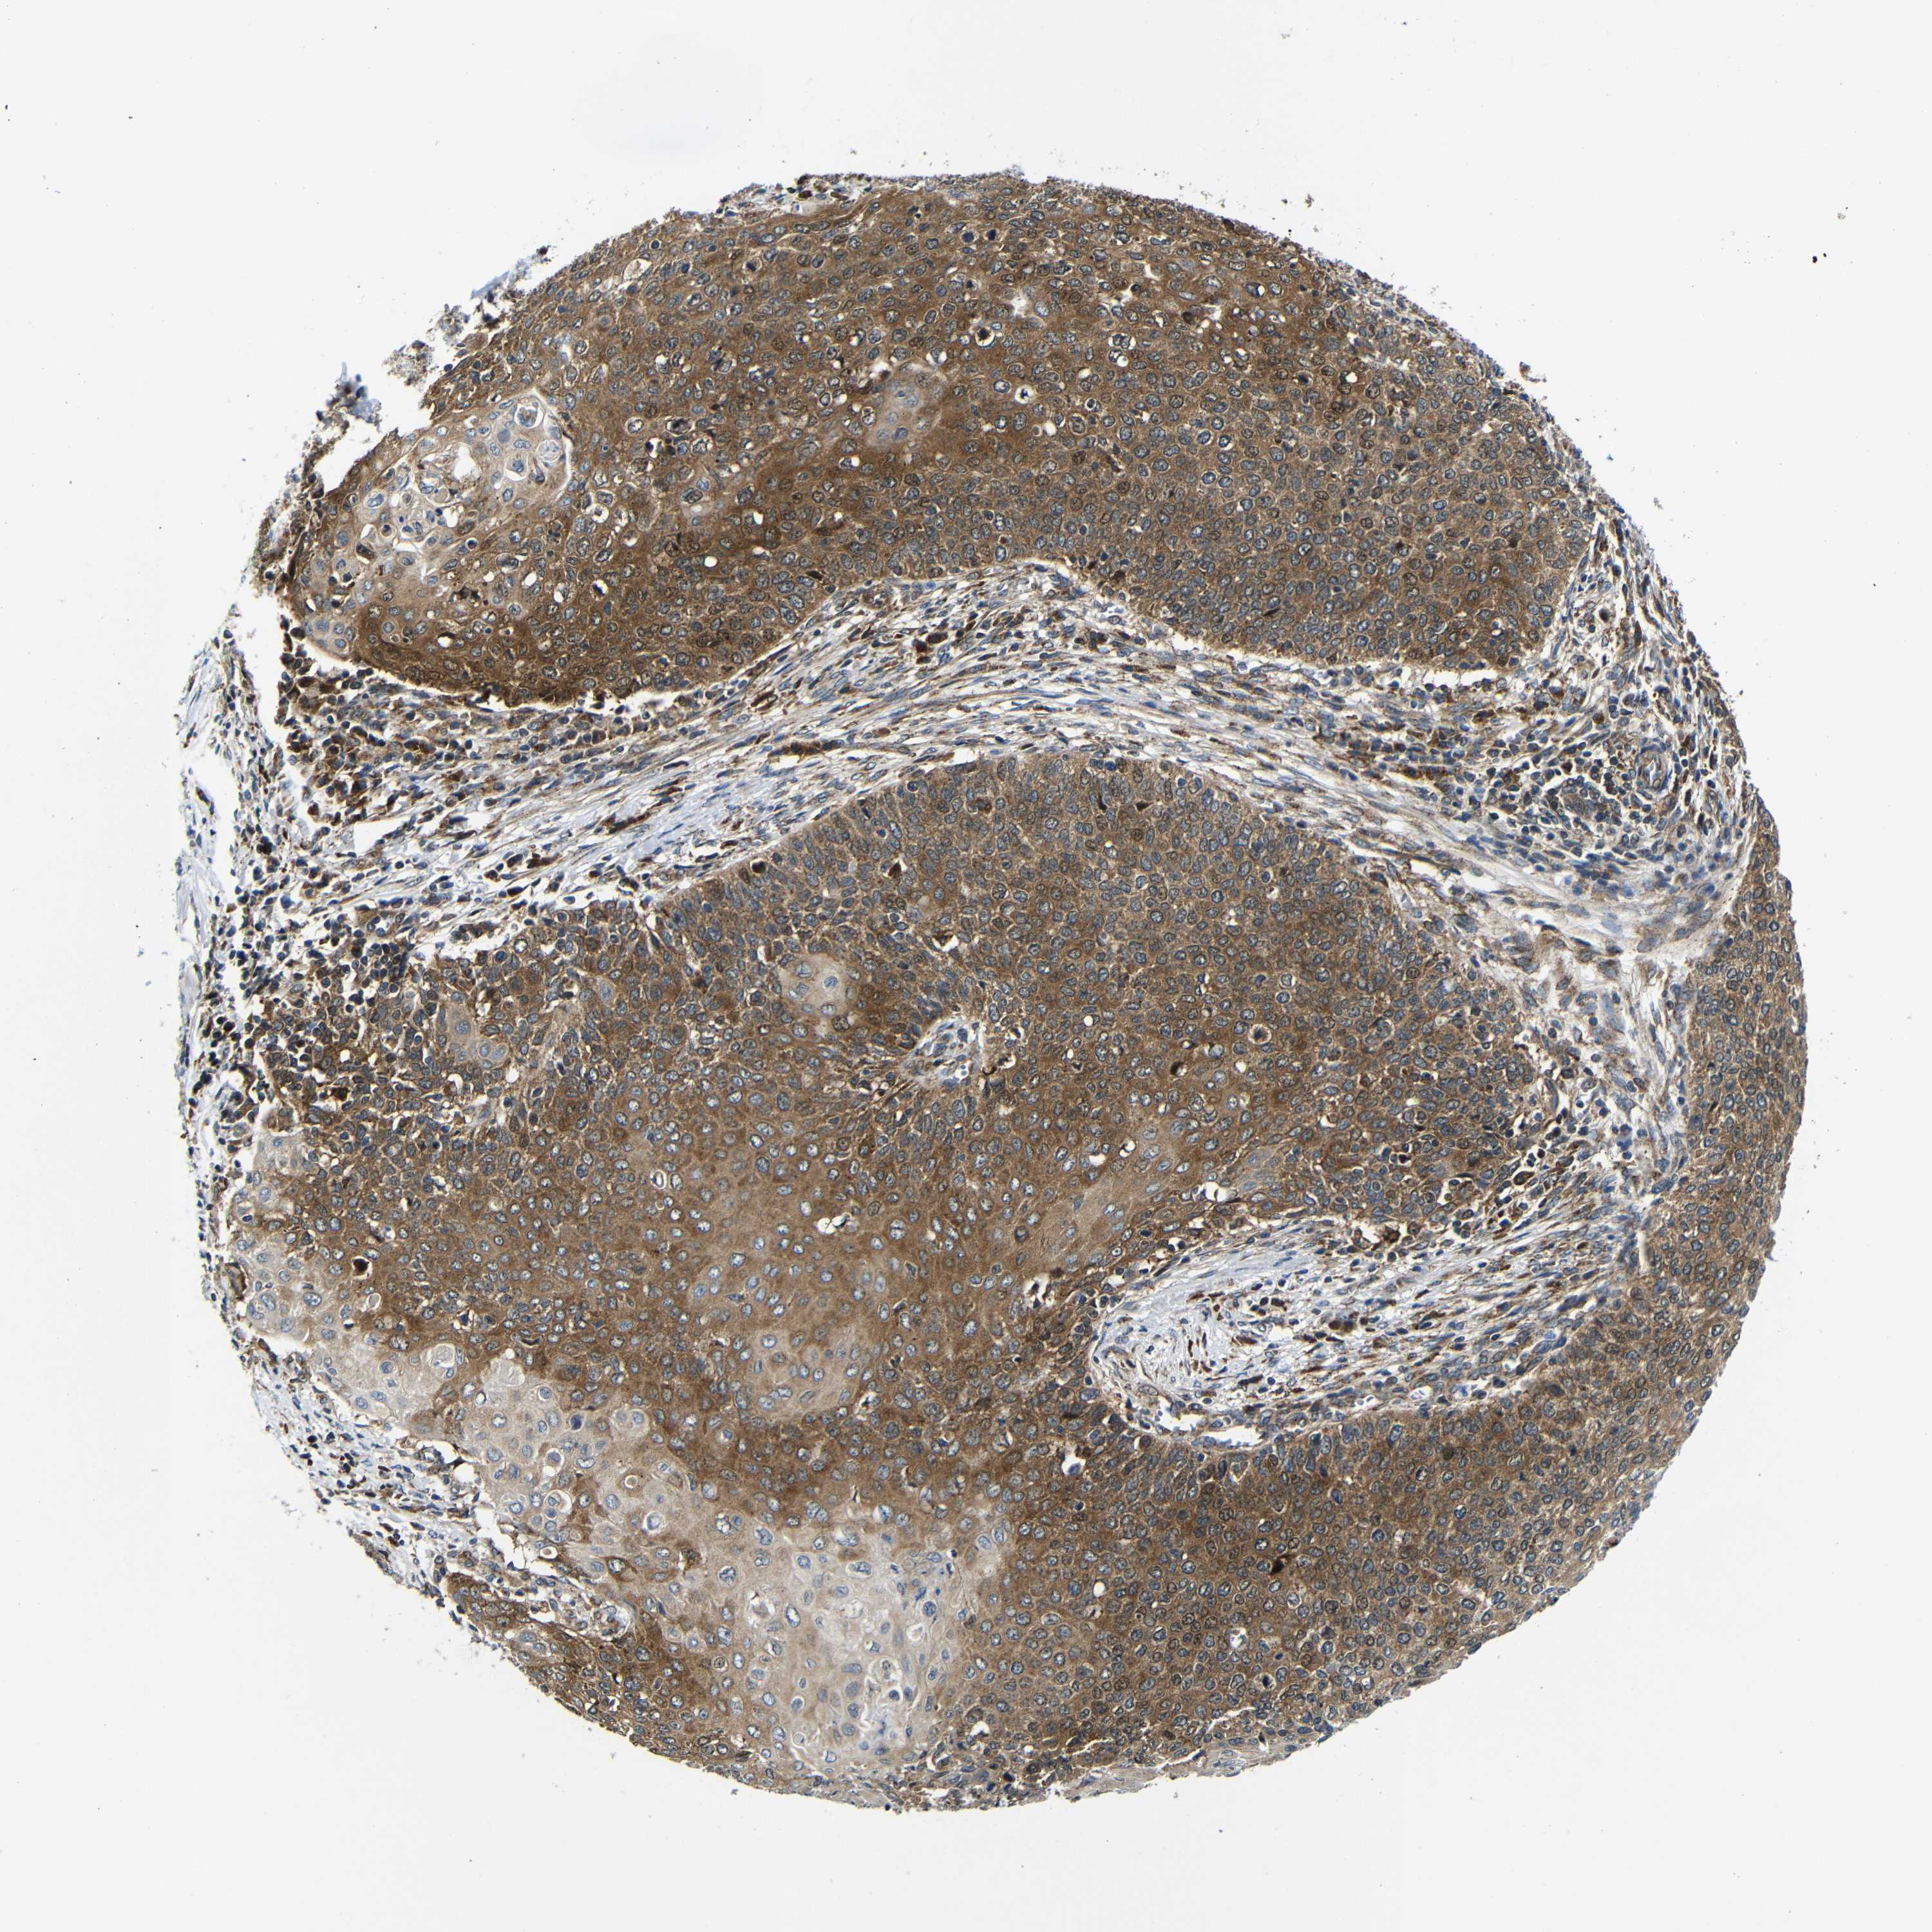

CERVICAL CANCER - Protein expressioni

A mouse-over function shows sample information and annotation data. Click on an image to view it in a full screen mode. Samples can be filtered based on level of antibody staining by selecting one or several of the following categories: high, medium, low and not detected. The assay and annotation is described here.

Note that samples used for immunohistochemistry by the Human Protein Atlas do not correspond to samples in the TCGA dataset.

Antibody stainingi

Antibody staining in the annotated cell types in the current human tissue is reported as not detected, low, medium, or high, based on conventional immunohistochemistry profiling in selected tissues. This score is based on the combination of the staining intensity and fraction of stained cells.

Each image is clickable and will lead to virtual microscopy that enables deeper exploration of all samples and also displays staining intensity scores, fraction scores and subcellular localization as well as patient and tissue information for each sample.

Antibody CAB012476

Staining

High

Medium

Low

Not detected

Intensity

Strong

Moderate

Weak

Negative

Quantity

>75%

75%-25%

<25%

None

Location

Nuclear

Cytoplasmic/membranous

Cytoplasmic/membranous,nuclear

Squamous cell carcinoma, NOS

Adenocarcinoma, NOS